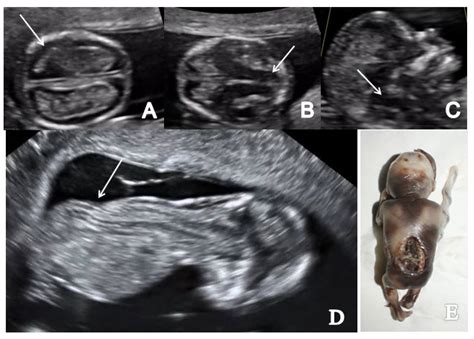

• Evaluating the nuchal translucency, a fluid-filled space at the back of the baby’s neck, which can indicate certain chromosomal abnormalities.

• Nuchal Translucency Measurement: The technician will measure the thickness of the nuchal translucency, which is an important indicator of the baby’s health. This measurement, along with other factors, helps assess the risk of chromosomal abnormalities like Down syndrome.

• Nuchal Translucency: The thickness of the nuchal translucency is compared to standard values to assess the risk of chromosomal abnormalities.

• Nuchal Translucency Thickness: The measurement of the nuchal translucency can vary, and a thicker measurement may indicate a higher risk of chromosomal abnormalities.